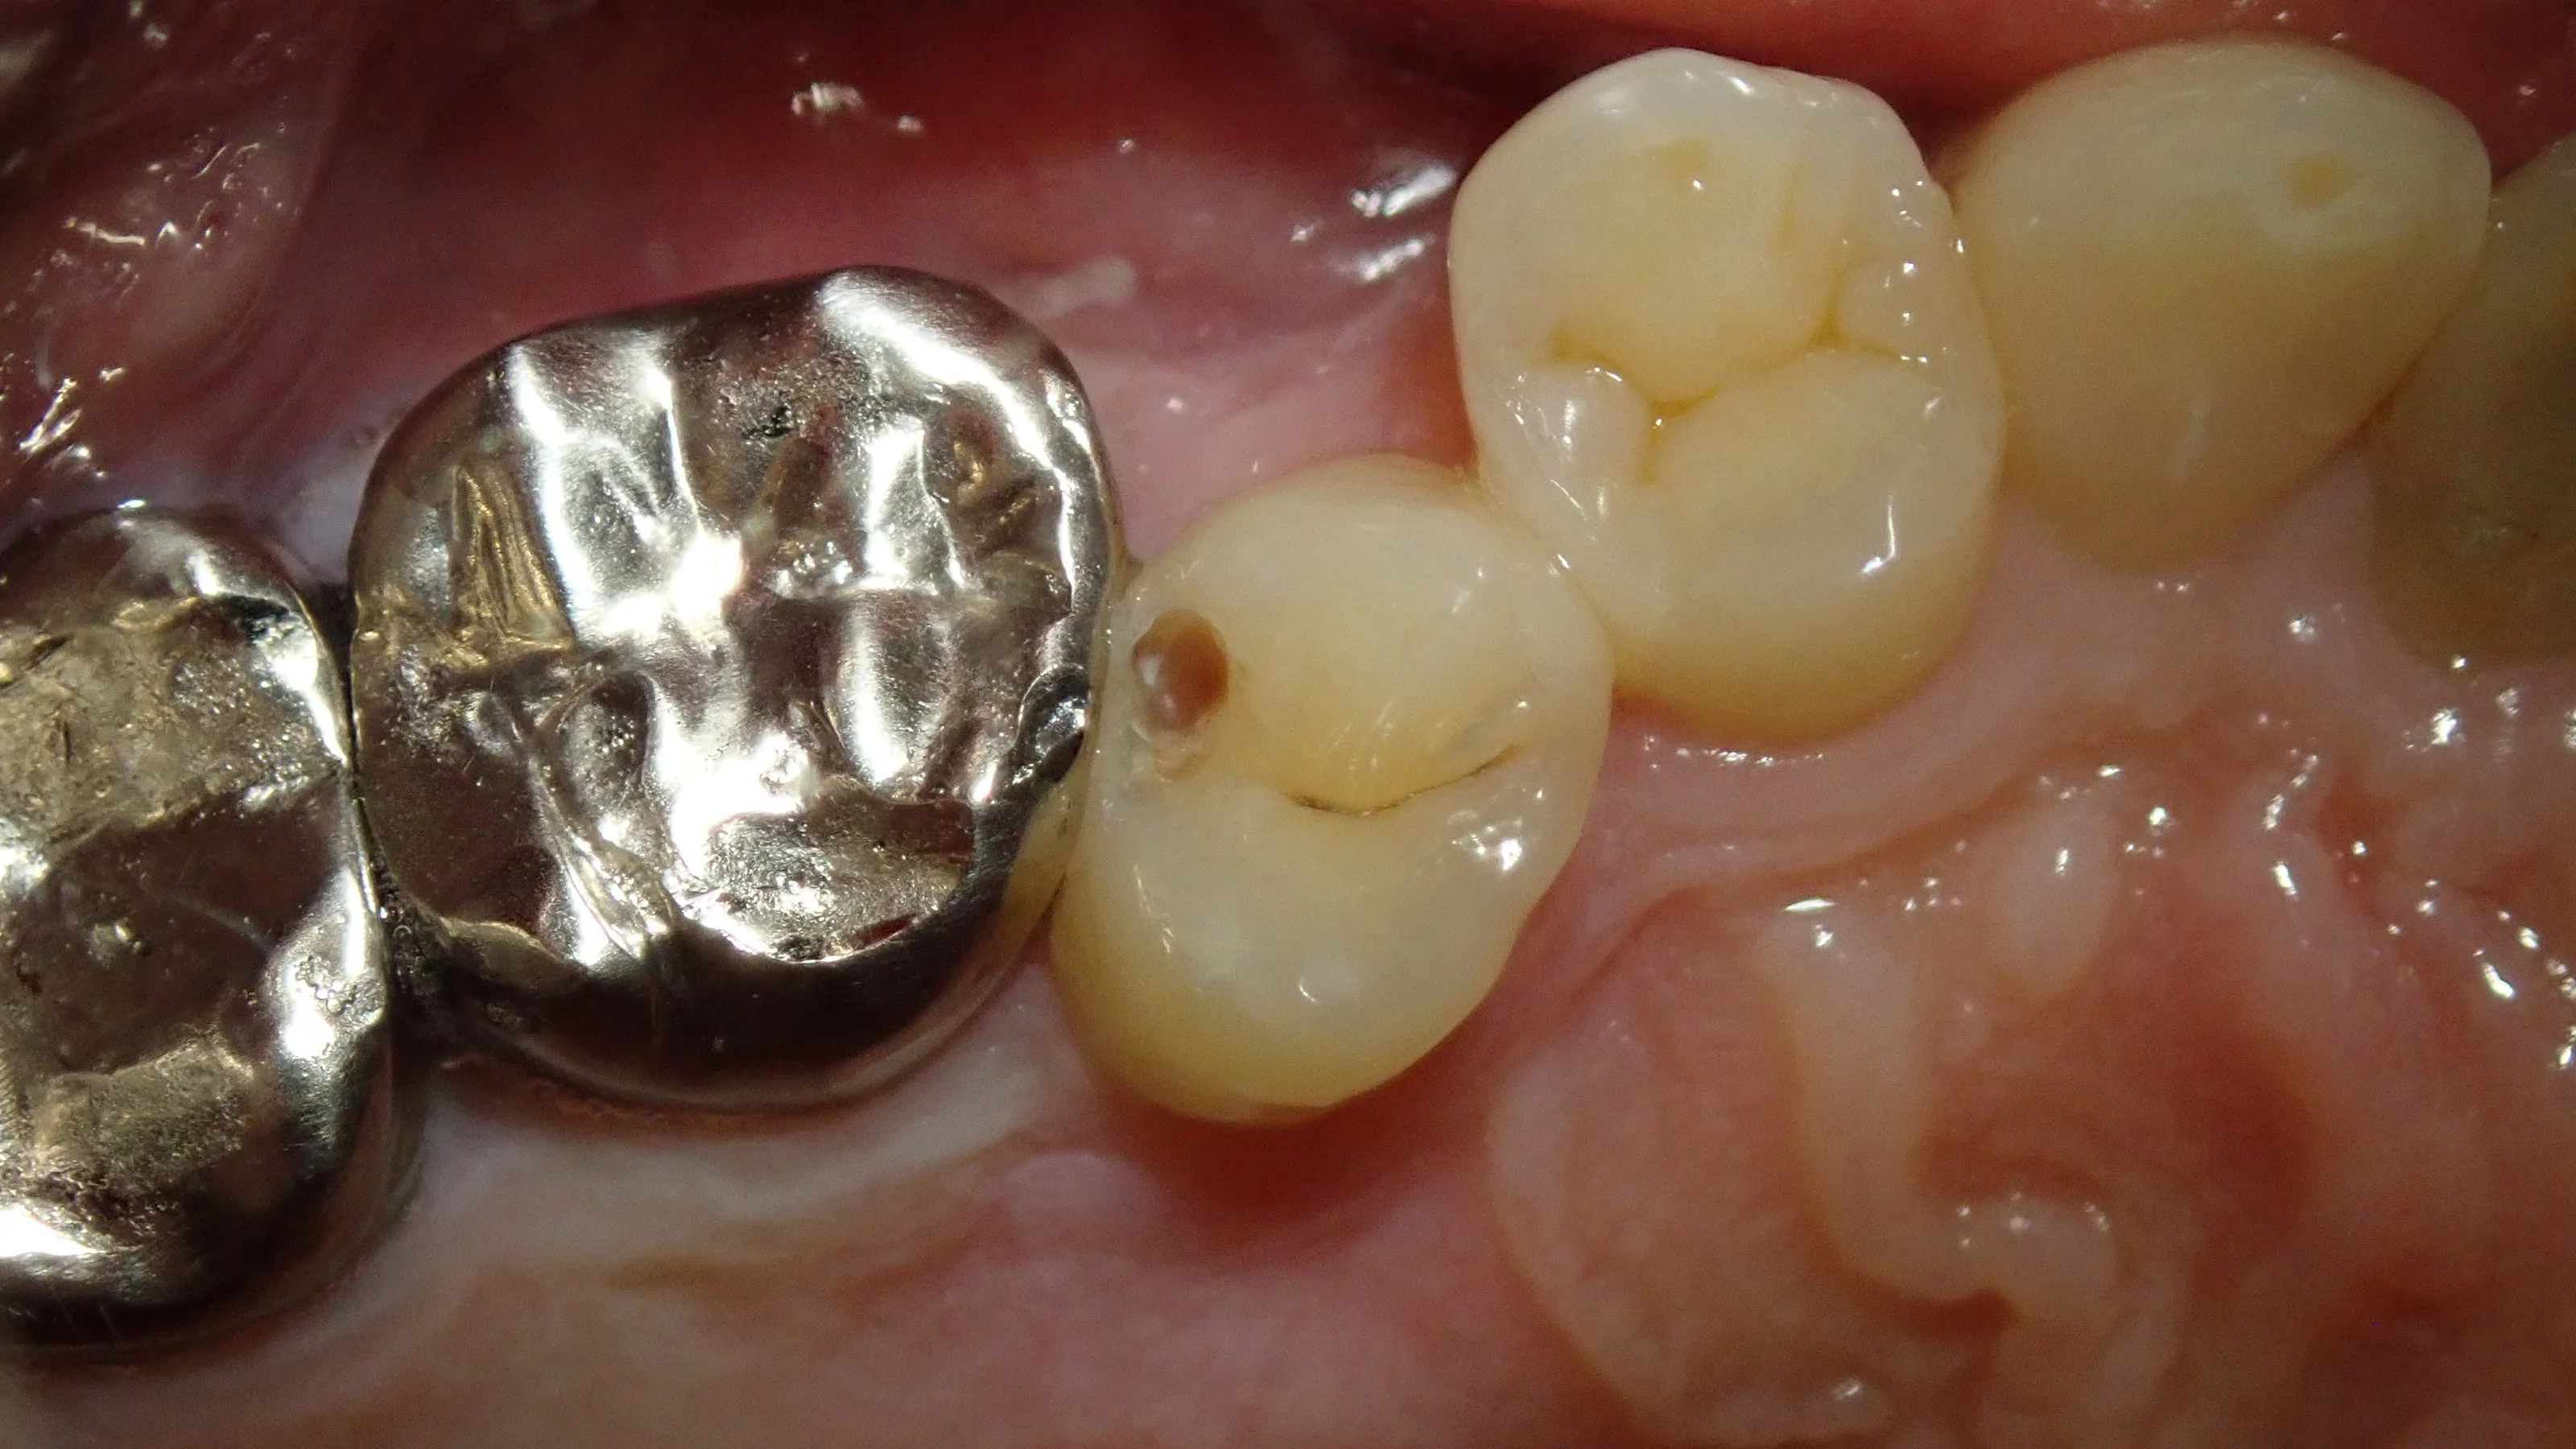

軽く詰め物や歯の表面を削ったのがこちらです。

中が明らかに黒っぽくなっているのが分かるかと思います。